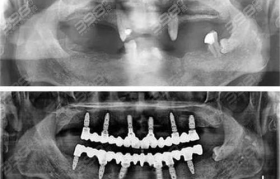

满口种植牙是一项复杂的口腔修复手术,其费用受多种因素影响。本文将详细解析满口种植牙的价格构成、影响因...